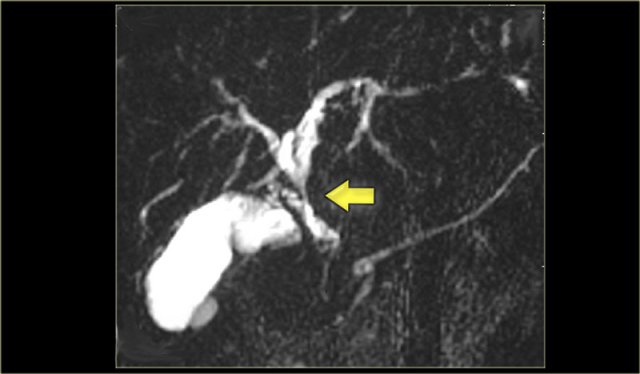

On the left a MRCP in a pateint with PSC.

Notice the large stricture, which is quite worriesome for cholagiocarcinoma (arrow).

The strictures in PSC show an abrupt transission, while here we see 'shouldering', which indicates mass-efect.

In addition there is intrahepatic dilatation proximal to this stenotic area.